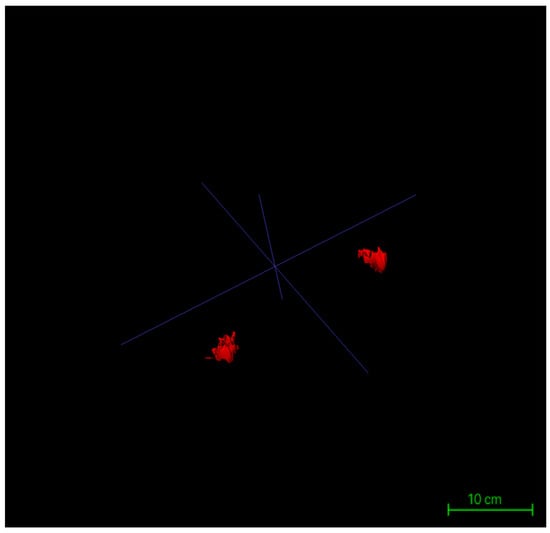

Following the completion of three-dimensional segmentation of glandular and intramammary adipose tissues, three-dimensional surface reconstruction was performed using the built-in visualization module of ITK-SNAP 4.0. Based on the label maps generated during segmentation, the software automatically created surface meshes for each labeled structure, rendering the spatial morphology of glandular and adipose tissues in three-dimensional coordinates. This reconstruction process was conducted directly on high-resolution DICOM-format MRI datasets, with the original matrix size preserved at 384 × 384 pixels, in-plane resolution of 0.9375 mm × 0.9375 mm, and a slice thickness of 5 mm across 30 contiguous slices. By maintaining these native imaging parameters throughout the modeling process, anatomical continuity and structural fidelity were ensured (Figure 5).

Figure 5.

Workstation interface showing the completed 3D reconstruction of bilateral glandular tissues.

Surface rendering was implemented using the Marching Cubes algorithm, the default method in ITK-SNAP, which converts each labeled region into a polygonal mesh. Glandular and adipose tissues were visualized with distinct color codes corresponding to their label IDs, and the resulting models could be rotated, zoomed, and sectioned interactively within the 3D viewer. Following model generation, the reconstructed structures were rigorously verified using synchronized axial, sagittal, and coronal views. Operators examined the alignment of each three-dimensional surface boundary against its corresponding two-dimensional slices to ensure spatial consistency, structural closure, and boundary integrity. This step provided the foundational quality assurance necessary for subsequent volumetric analysis and image-based quantitative assessments (Figure 6).

Figure 6.

Three-dimensional reconstruction models of bilateral glandular tissues in a representative patient.